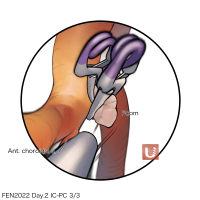

FEN2022シリーズ